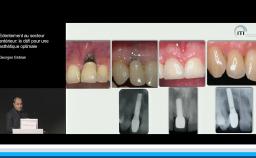

Tous les types d’implants peuvent être utilisés en secteur antérieur, mais l’utilisation de connexions au niveau osseux offre plus de latitude sur le placement de l’implant et sur la réhabilitation prothétique. Afin de limiter les proximités entre implants et entre dents et implants, l’utilisation d’implants de faible diamètre et la réduction du nombre d’implants sont des options à considérer.

• de choisir le type et le nombre d’implants à placer en secteur antérieur pour optimiser le résultat esthétique